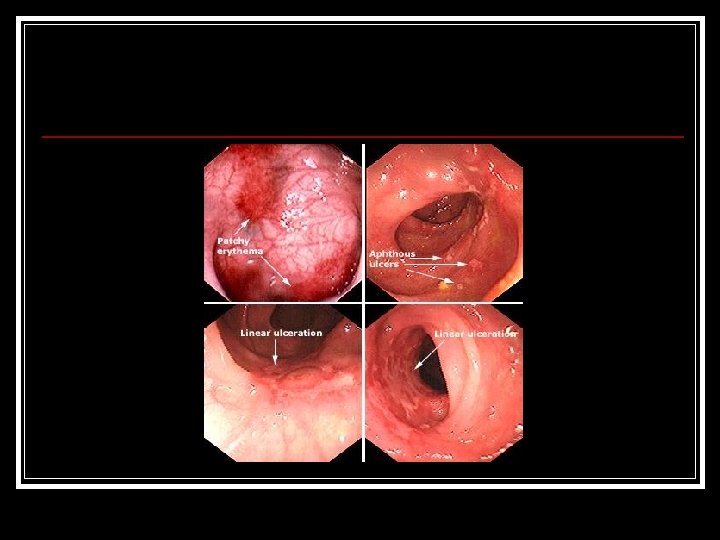

Cas clinique (001 -8) n Question n 3/ Quelles sont les caractéristiques endoscopiques de la maladie de Crohn ?

Cas clinique (001 -9) n Question n n 3/ Quelles sont les caractéristiques endoscopiques de la maladie de Crohn Réponse n Lésions macroscopiques à type de: n n n n n Ulcérations aphtoïdes Ulcérations en carte de géographie Pavage Erythème, œdème Pseudopolypes Sténoses Epaississement pariétal Fistule Distribution segmentaire, discontinue, transmurale Topographie n n Iléale : 30 à 40 % Iléo-colique : 30 à 50% Colique : 15 à 25 % Anale : 20 à 50 %